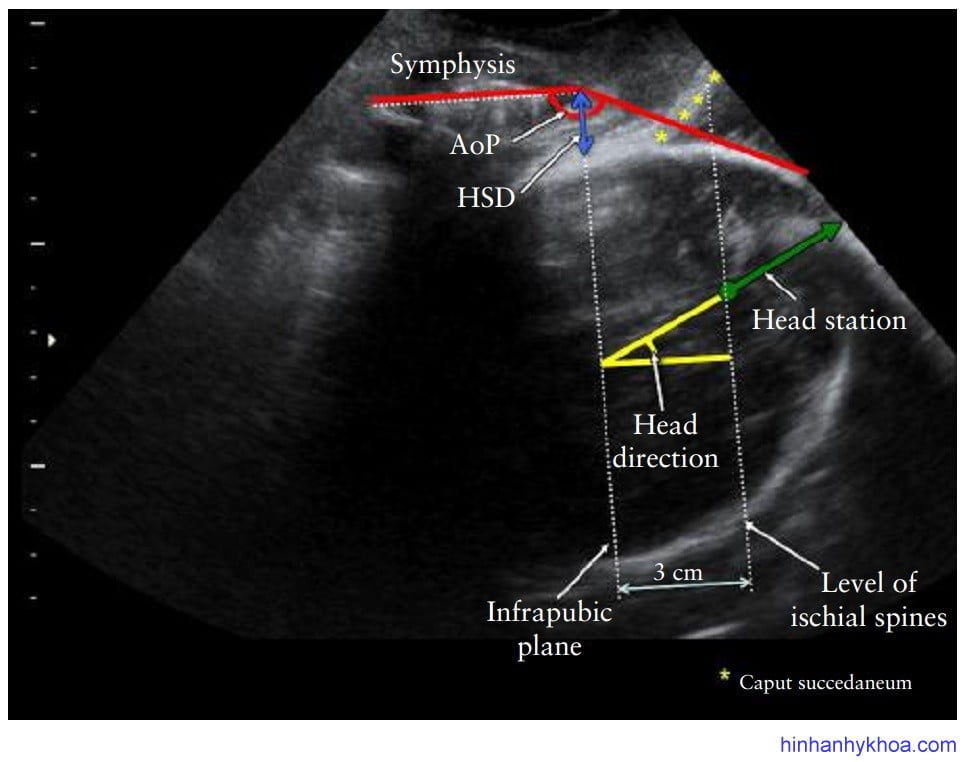

Thông thường, mốc giải phẫu truyền thống để các nhà lâm sàng tham chiếu khi thăm khám bằng tay qua âm đạo là mặt phẳng ngang mức hai gai chậu, sẽ không nhìn thấy được trên mặt cắt siêu âm này. Tuy nhiên, giữa phần thấp nhất của khớp mu và mặt phẳng ngang qua hai gai chậu có mối liên quan về giải phẫu: đường dưới mu (“infrapubic line”) là đường thẳng tưởng tượng kẻ từ vị trí thấp nhất của khớp mu, vuông góc với trục dọc khớp mu, hướng về phía ống sanh. Trên CT scan tái tạo dựng hình, đường dưới mu này nằm phía trên mặt phẳng ngang qua hai gai chậu khoảng 3cm [42,82-84].

Trên mặt cắt dọc giữa ở đáy chậu, có ba thông số được đề nghị để đánh giá trực tiếp độ lọt thai là: góc tiến triển (angle of progression = AoP) còn gọi là góc xuống40,43; khoảng cách tiến triển (progression distance = PD)30; và độ lọt siêu âm đáy chậu (transperineal ultrasound head station)41. Một vài thông số gián tiếp khác như: khoảng cách đầu – khớp mu (head – symphysis distance = HSD) thay đổi theo sự đi xuống của đầu thai51; và hướng đầu

thai cho biết hướng của trục dọc đầu thai so với trục dọc của khớp mu [42].

Góc tiến triển (AoP)/góc xuống: vẽ 2 đường thẳng: một là đường dọc theo trục xương mu, hai là đường vẽ từ phần thấp nhất của xương mu tiếp tuyến với phần thấp nhất của xương sọ thai. AoP là góc hợp bởi hai đường này (Hình 4).

Hướng đầu thai. Là dấu hiệu gián tiếp đánh giá độ lọt thai, được mô tả lần đầu tiên bởi Hendrich và cộng sự42, xác định bởi góc giữa trục dài nhất của phần đầu thai thấy được với trục dọc của xương mu ở mặt phẳng dọc giữa khi siêu âm qua ngã đáy chậu (Hình 5). Xếp loại: đầu đi xuống (góc < 00), đầu đi ngang (góc 0-300) và đầu đi lên (góc > 300). Các tác giả ghi nhận dễ dàng sự thay đổi của hướng đầu thai từ khi đi xuống hướng vào khung chậu, sau

Độ lọt trên siêu âm. Đọ lọt trên siêu âm qua ngã đáy chậu dùng để mô tả sự tiến triển của cuộc chuyển dạ (tính bằng centimet trên hay dưới mặt phẳng qua hai gai chậu) và có kết hợp với độ cong của ống sanh. Điều này đòi hỏi phải đánh giá: (i) hướng đầu thai và (ii) khoảng cách giữa đường dưới mu (đường thẳng nằm trên mặt phẳng qua hai gai chậu 3cm) với phần xương sọ xuống thấp nhất dọc theo trục của hướng đầu thai (Hình 6). Độ lọt trên siêu âm đáy chậu khi được so sánh với các thông số khác để đo độ lọt thai thì thấy phức tạp hơn nhiều do phải đo đạc nhiều yếu tố (bao gồm cả góc và khoảng cách). Do đó, người ta đã tìm ra mối tương quan cho phép chuyển đổi trực tiếp từ góc tiến triển AoP sang độ lọt đo bằng centimet (Bảng 1).

Hình 6: độ lọt trên siêu âm đáy chậu được đo dọc theo hướng đầu thai. Góc tiến triển AoP, khoảng cách đầu – khớp mu (HSD), đường dưới mu, và mặt phẳng qua hai gai chậu cũng được thể hiện trên hình (Tutschek và cộng sự [32]).